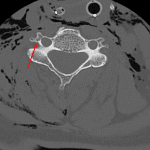

- Acute nondisplaced right C4 transverse process fracture

- Nondisplaced right C4 transverse process fracture

Acute nondisplaced right C4 transverse process fracture.